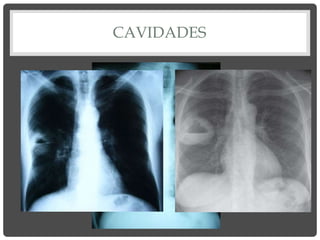

3. CAVIDADES

Opacidad periférica con centro radiolúcido.

Puede ser única o cavidades múltiples,

dependiendo de la etiología.

Causas

• Infecciosas: absceso, TBC, micosis, parásitos

(quiste hidatídico).

• No infecciosas: Sarcoidosis, G. de Wegener,

AR, quiste broncogénico, bronquiectasias

quísticas.

• Neoplasias: tumores abscedados.

CAVIDADES